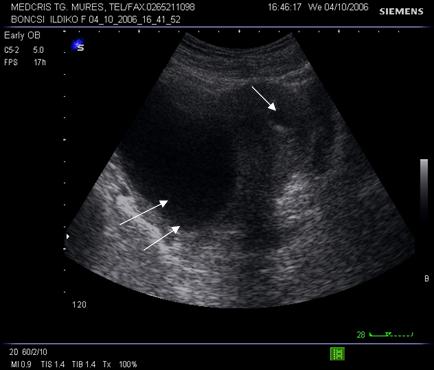

Fig. nr. 9 Sarcina de 5 saptamani la ecografia abdominala.( sacul ovular marcat cu o sageata ) Se remarca retrouterin o formatiune anecogena de peste 5 cm ( chist ovarian marcat cu doua sageti )

Fig. nr. 96. Aceeasi sarcina ca in figura precedenta, retrouterin chist ovarian evident la ecografia transvaginala